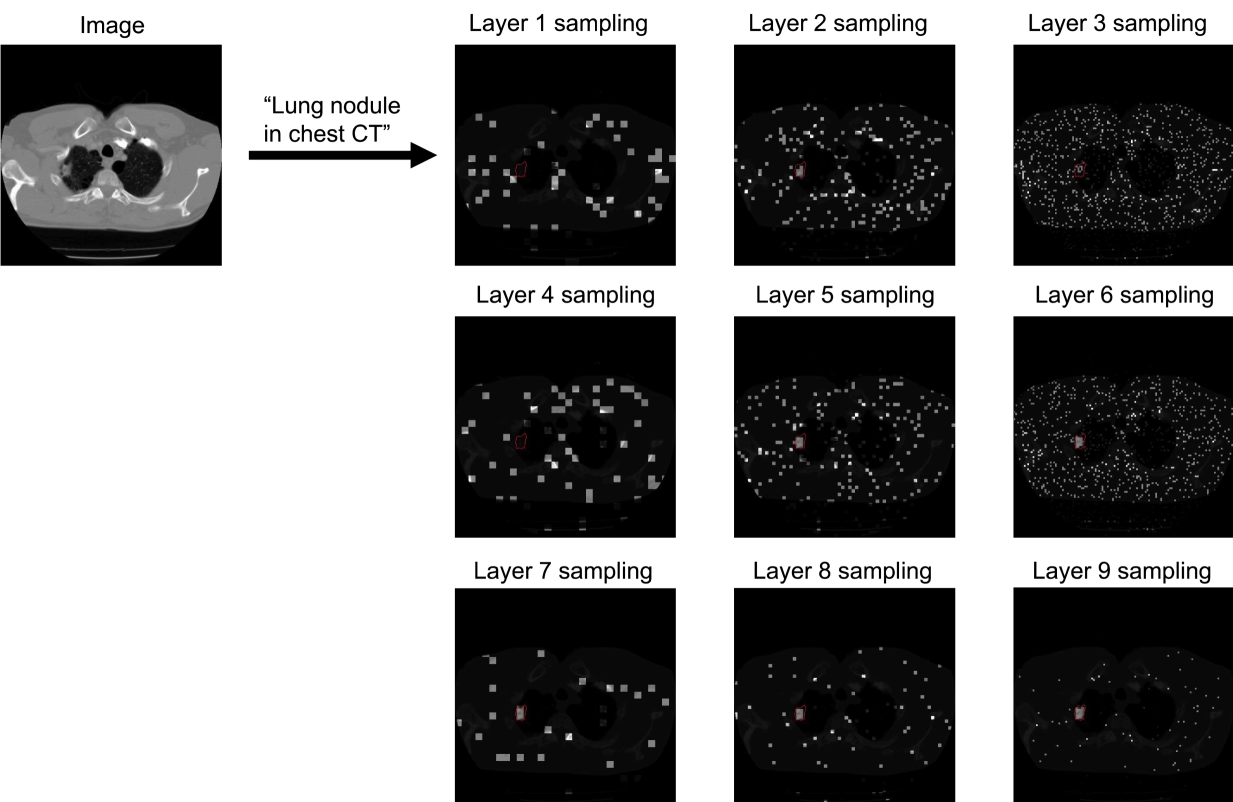

From Fig. 5, 6, 7 and 8 we can see that the sampling is wide spread during the early layers. The sampling began to concentrate towards the target region during the middle layers, while still exploring the other regions. At the final layers the sampling was highly concentrated on the target regions.

Figure 5: Boltzmann sampling example for lung nodule in chest CT. The sample patches are bright with target region circled in red.

We visualize the examples of Boltzmann attention sampling through the layers in BoltzFormer. In each layer, each query vector only attend to the sampled visual features visualized in the figures. We looped through the three scales of visual features for three times, resulting in nine layers in total. The shaded regions are completely invisible to the query in that layer. We show the Boltzmann sampling for the first query in the ensemble in these examples.